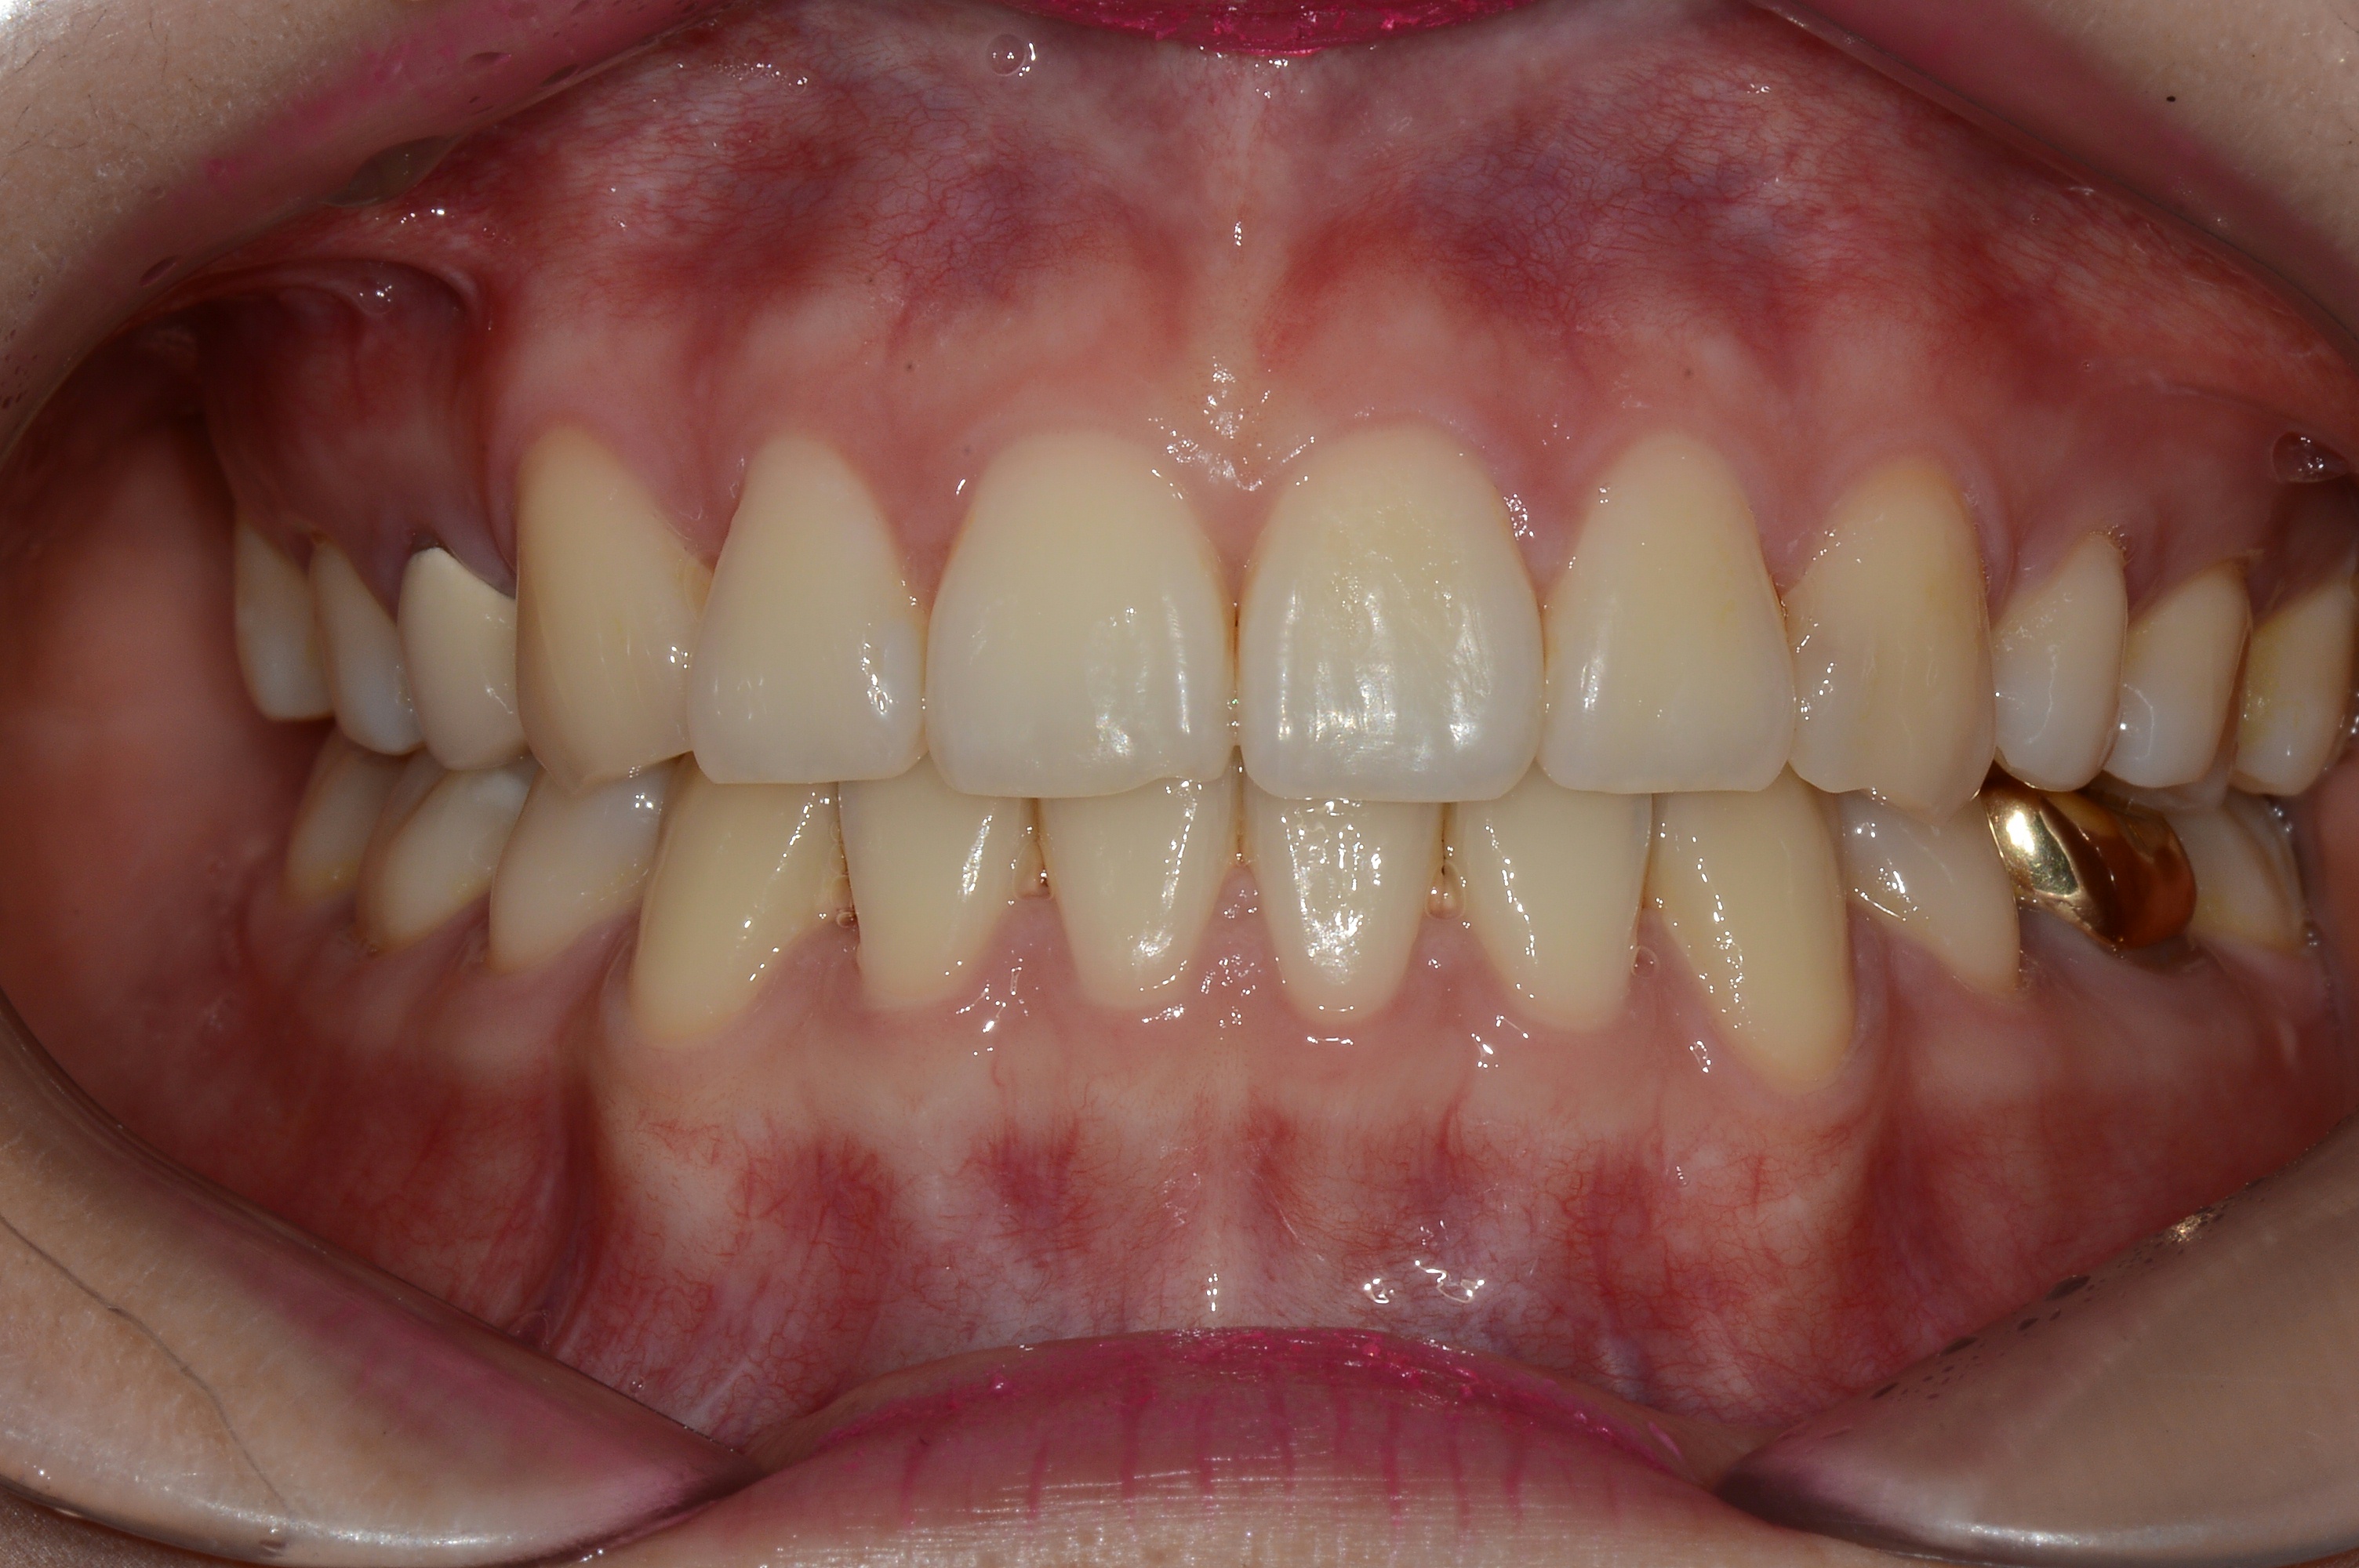

치료 전 사진입니다.